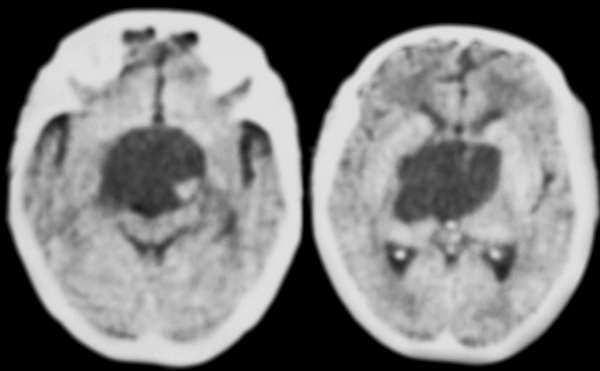

患者女,51岁,表情呆滞,反应迟钝,临床医生怀疑脑病,先来做了ct。囊性病灶ct值与脑脊液近似。

ct扫描显示:中线部位鞍上可见一圆形低密度病变,边缘清晰,密度尚均匀,ct值与脑脊液相仿,囊内左后是点状钙化影,病变向下葡行生长至脚间池,脑干受压变形;脑室系统未见明显异常.

诊断意见:鞍上囊性占位性病变,多考虑表皮样囊肿.

鉴别:此病例主要与囊性颅咽管瘤:钙化多为条状或蛋壳样,形态规整,无蒲行生长特性.